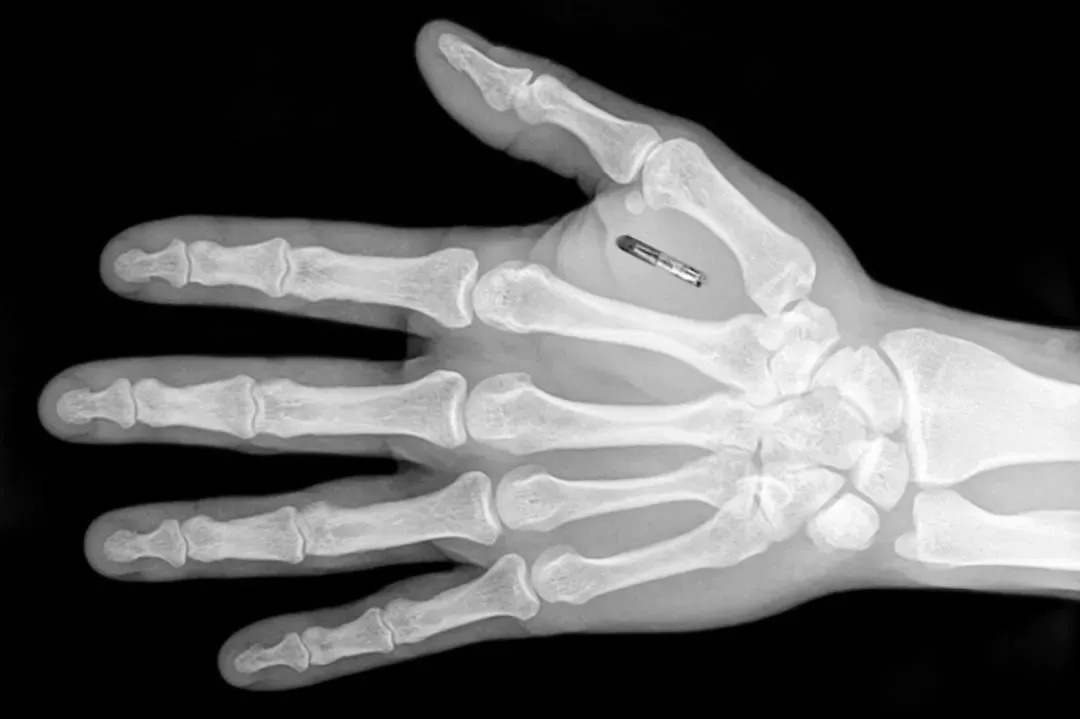

在瑞典,为了免去出入公司掏卡开门的麻烦,一些人还在自己的手掌中植入了米粒大小的RFID芯片,从此进出门禁只需挥一挥手。除了门禁换锁需要剁手以外,在手掌中植入门禁信息的点子无疑为人们的生活带去了便利。

你好!就握个手,手机咋解锁了?| independent.co.uk